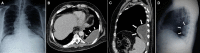

With CT (computed tomography) chest gaining more importance as a diagnostic tool, chest X-ray especially the lateral view is taken less commonly nowadays. Besides CT chest is also proven to be superior to chest X-ray in patients with major blunt trauma. We are presenting a 68-year old male who was partially treated from outside for a left sided pneumonia. He came to our hospital because of persisting chest pain. Chest X-ray, frontal view (postero-anterior) was almost normal except for a mild opacity in the left lower zone. CT scan of the chest revealed a fluid collection posteriorly enclosed within enhancing pleura. Chest X-ray, left lateral view showed a corresponding posterior pleural based opacity. We are presenting this case to highlight the importance of the lateral view of the chest X-ray. In selected cases there is still a role for the lateral view. With the three dimensional visualization provided by the CT, the lateral view of the chest may be easier to understand. Consequent to the initial diagnosis by CT further follow up can be done with the chest X-ray. In a limited way this mitigates unnecessary expenditure and more importantly prevents the patient from exposure to harmful radiation in the form of repeated CT.